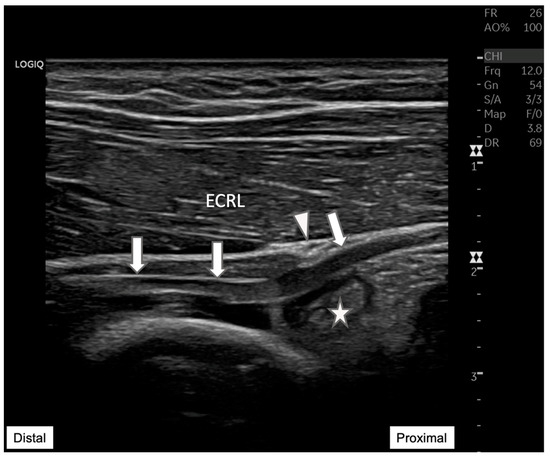

Figure 5. Follow-up ultrasound evaluation of the radial nerve in the forearm. This ultrasound image provides a clear view of the radial nerve (arrow) after an aspiration procedure targeting a synovial cyst (star). PIN at the Arcade of Frohse (arrowhead), where prior significant compression has been notably alleviated following the intervention and the path of the nerve, which had a reduced impingement. The previously larger cyst, which has been markedly reduced in size due to successful aspiration. This image demonstrates the effectiveness of ultrasound-guided interventions in managing compressive neuropathies. ECRL: Extensor carpi radialis longus. Previous reports of PIN compression caused by synovial cysts at the Arcade of Frohse are limited. Boushabi et al. [7] highlighted a case diagnosed using MRI, where surgical excision successfully relieved compression and restored motor function without recurrence. Another study [8] involving eight patients with PIN palsy identified synovial cysts as the cause in most cases. Diagnosis The diagnosis was confirmed through clinical examination, ultrasound, and MRI, with all patients undergoing surgical decompression. Complete recovery was achieved in all cases within a median of 12 months. However, no studies have specifically explored the use of aspiration for treating elbow synovial cysts, as existing reports focus on surgical approaches. While evidence on aspiration for elbow synovial cysts is lacking, insights can be drawn from studies on synovial cysts in other anatomical regions. For instance, Facet joint synovial cysts in the lumbar spine have been successfully treated with aspiration, with one report demonstrating sustained symptom relief over 24 months using a percutaneous two-needle approach under fluoroscopic guidance [9]. In contrast, a prospective study [10] on hip synovial cysts found that needle aspiration provided faster recovery and short-term relief but lacked durability, highlighting the variability of outcomes depending on the anatomical location. For elbow synovial cysts, evidence on recurrence rates and functional recovery remains scarce. Ultrasound-guided aspiration has been shown to be safe when careful visualization prevents injury to adjacent neural structures. In contrast, the risk of iatrogenic PIN injury during surgical resection is not well-documented. Further research is warranted to assess the long-term efficacy and safety of aspiration versus surgical excision for elbow synovial cysts.